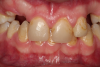

Fig 6. Photograph, 18-year-old brother.

Figure 6

Fig 8. Photograph, 14-year-old brother.

Figure 8

Figure 5 through Figure 12 exemplify what currently may present in private dental practices with these types of patients. Four brothers aged 14 years to 27 years all suffered from obstructed airways; high incidence of caries of dentin, enamel, and cementum; moderate periodontal disease; collapsed vertical; undiagnosed OSA; and the potential for increase in comorbidities such as diabetes, cardiovascular disease, dementia, cancer, high blood pressure, and others. Symptomology was presented throughout the young lives of the brothers in this family. The parents were unaware that the dental agenesis and premature permanent tooth extraction could have led their sons into severe health issues as they matured.

Swift intervention took place with caries control, periodontal care, orthodontic evaluation for arch form development to aid in the development of facial bones and creating an improved upper airway with nasal patency. These interventions were followed up with definitive implant therapies and rapidly advancing restorative technology and materials. Thus, not only were these young men's smiles restored, they also were provided with the opportunity to regain their dignity when they become confident with their new smiles.